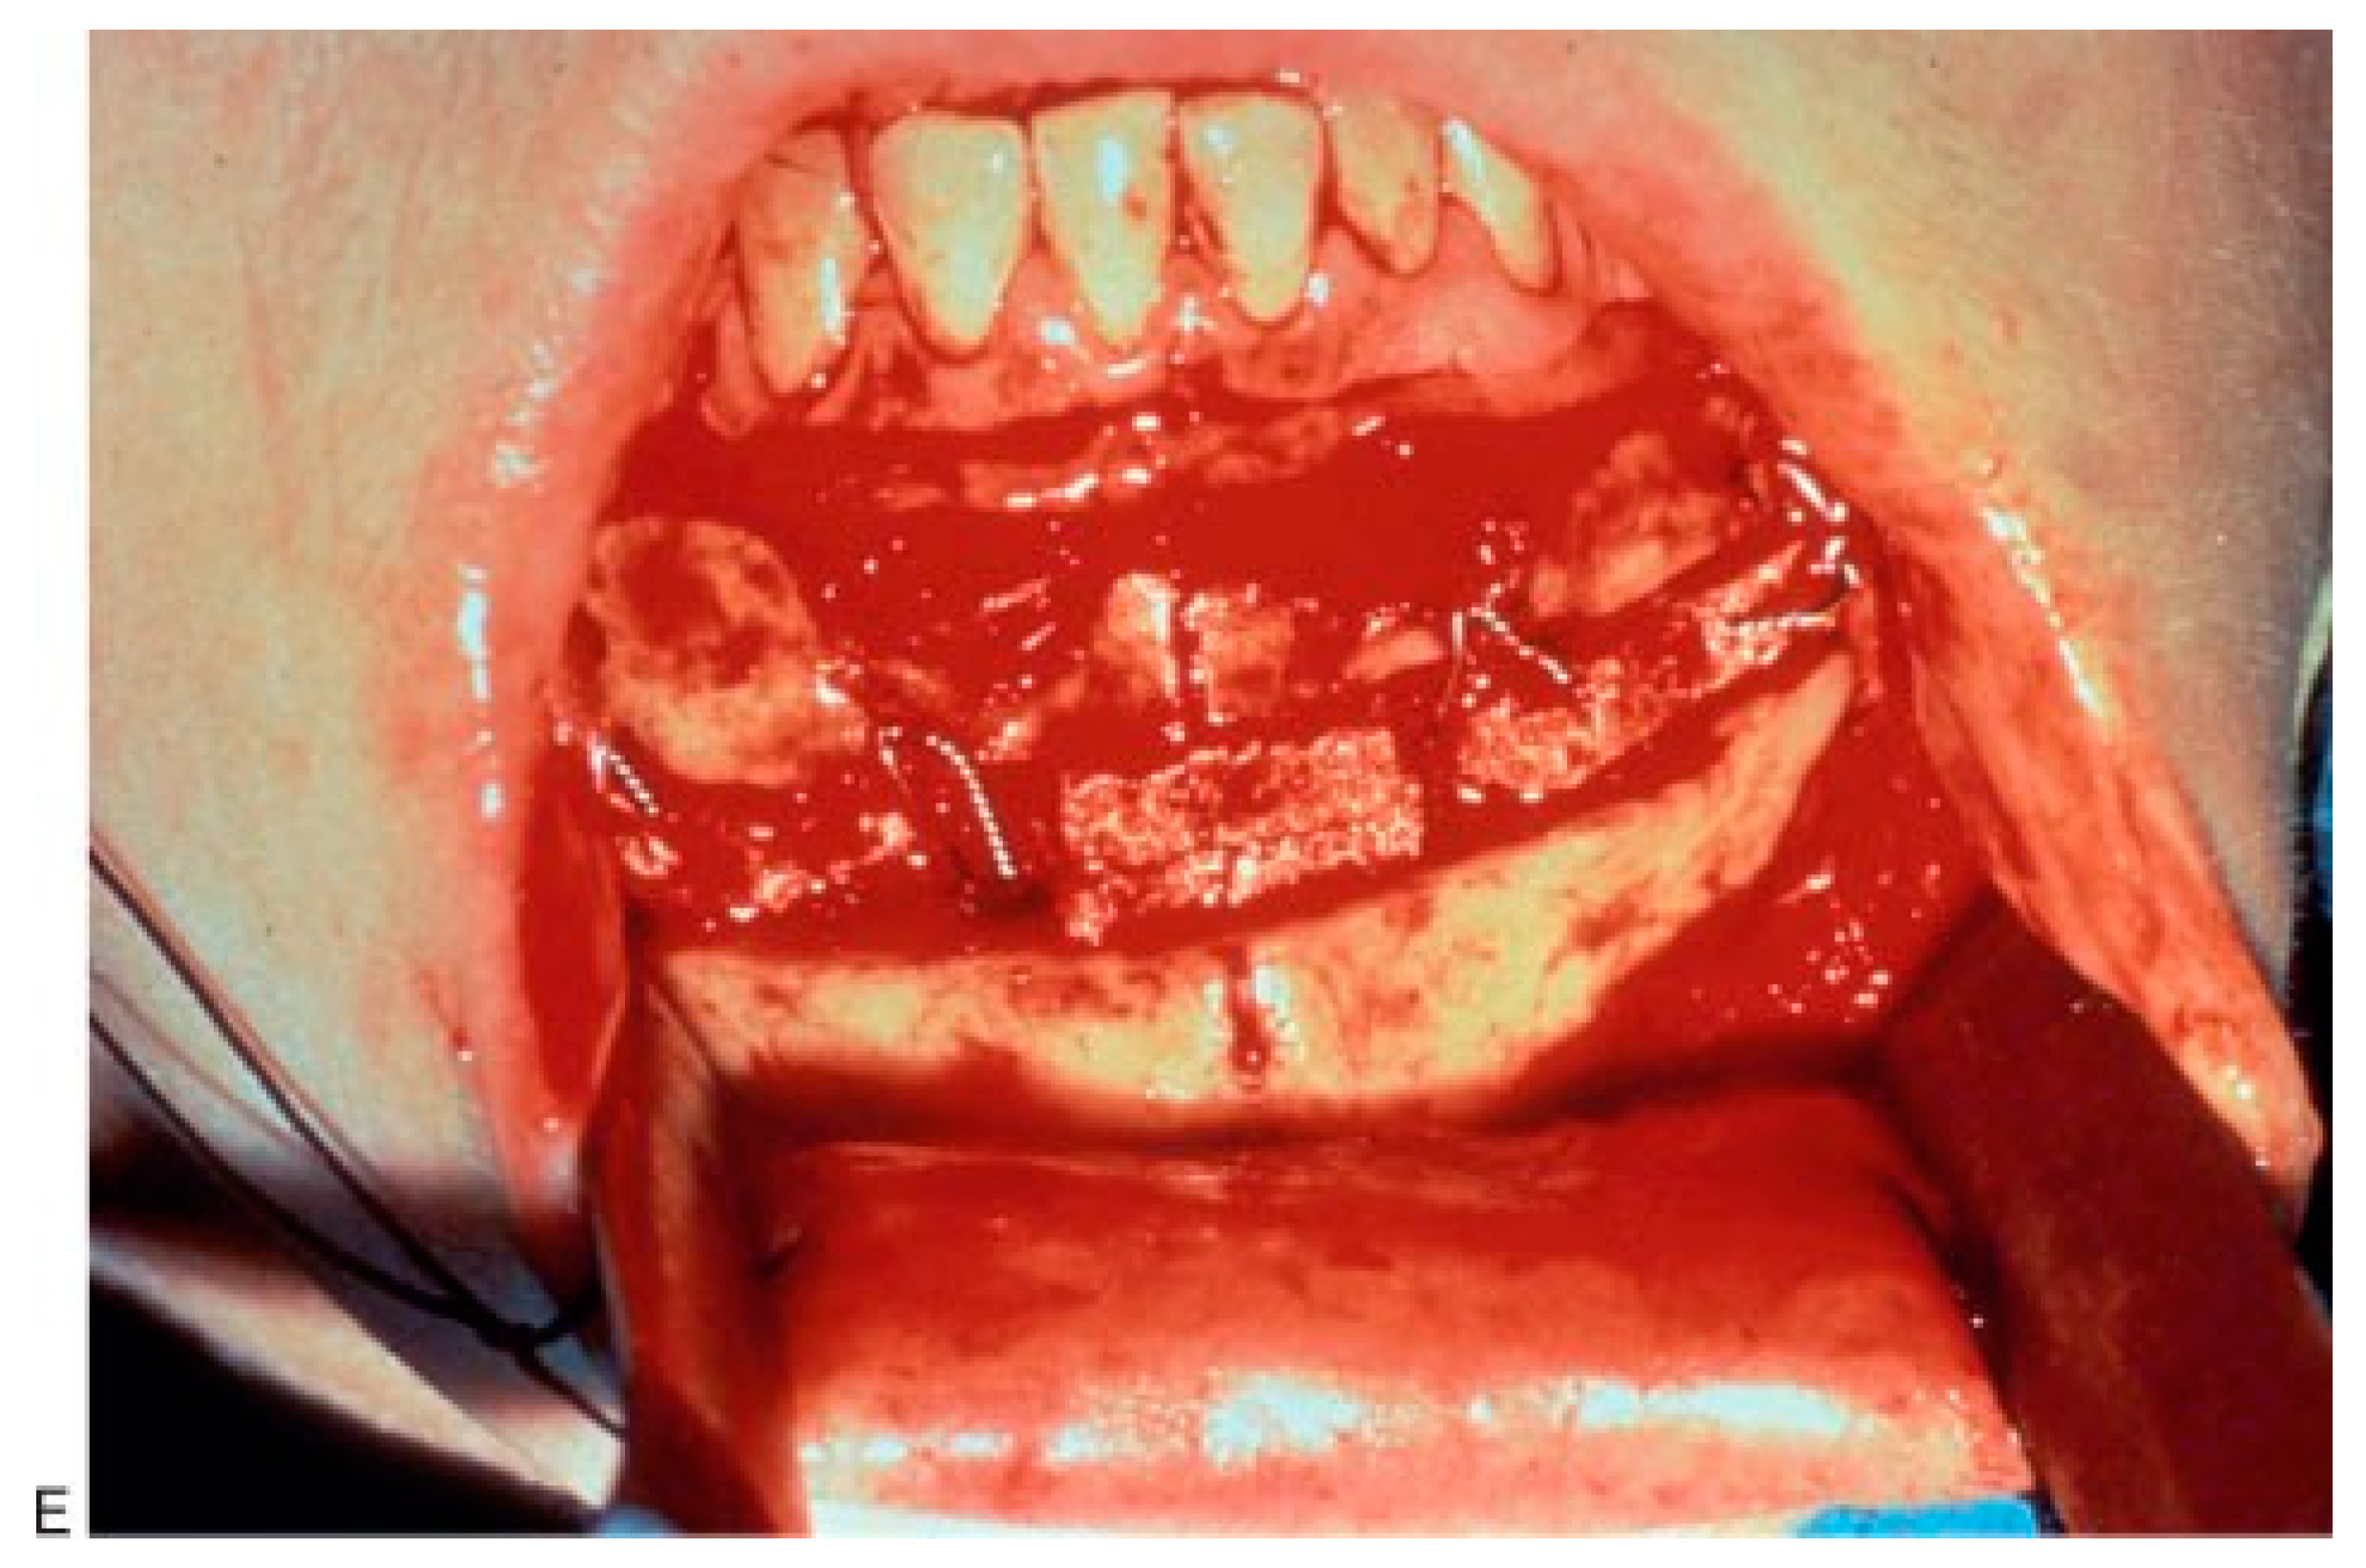

Figure 1.

(A,B) Masseteric hypertrophy and vertical microgenia. Correction was performed by gonial angle resection bilaterally and vertical lengthening genioplasty using block hydroxyapatite. Front and profile views after surgery. (C,D) Frontal and profile views 8 years later. (E) Intraoperative view of vertical lengthening genioplasty using block hydroxyapatite. (Reprinted with permission from Zins JE, et al. Contour alteration of the facial skeleton. In: Achauer BM, Guyuron B, eds. Plastic Surgery: Indications, Operatons, Outcomes. Philadelphia: Elsevier; 2000:2824. Copyright Elsevier 2000.).